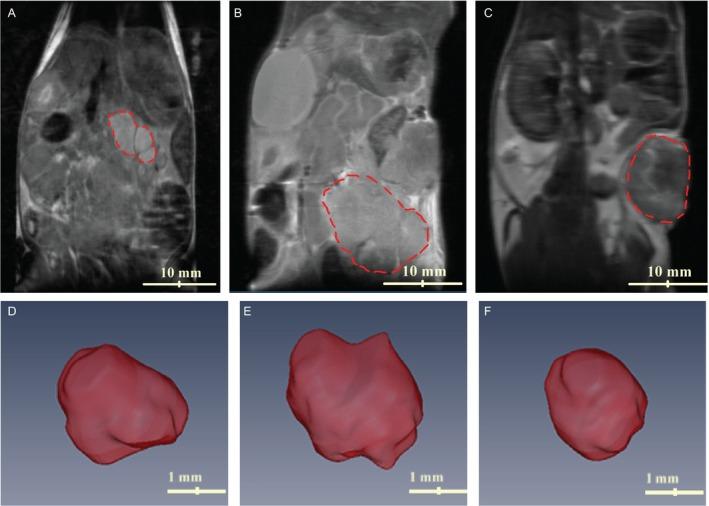

Noninvasive characterization of pancreatic tumor mouse models using magnetic resonance imaging.

The preclinical models of pancreatic adenocarcinoma provide an alternative means for determining the mechanisms of malignancy and possibilities for treatments, thus representing a resource of immense potential for cancer treatment in medicine. To evaluate different tumor models, quantifiable magnetic resonance imaging (MRI) techniques can play a significant role in identifying valuable in vivo biomarkers of tumor characteristics. We characterized three models of pancreatic cancer with multiparametric MRI techniques. Tumor stromal density of each tumor was measured using diffusion-weighted imaging and magnetization transfer (MT-MRI). Histologic measurement showed a similar trend with tumor fibrosis levels. Results indicated that MRI measurements can serve as a valuable tool in identifying and evaluating tumor characteristics.